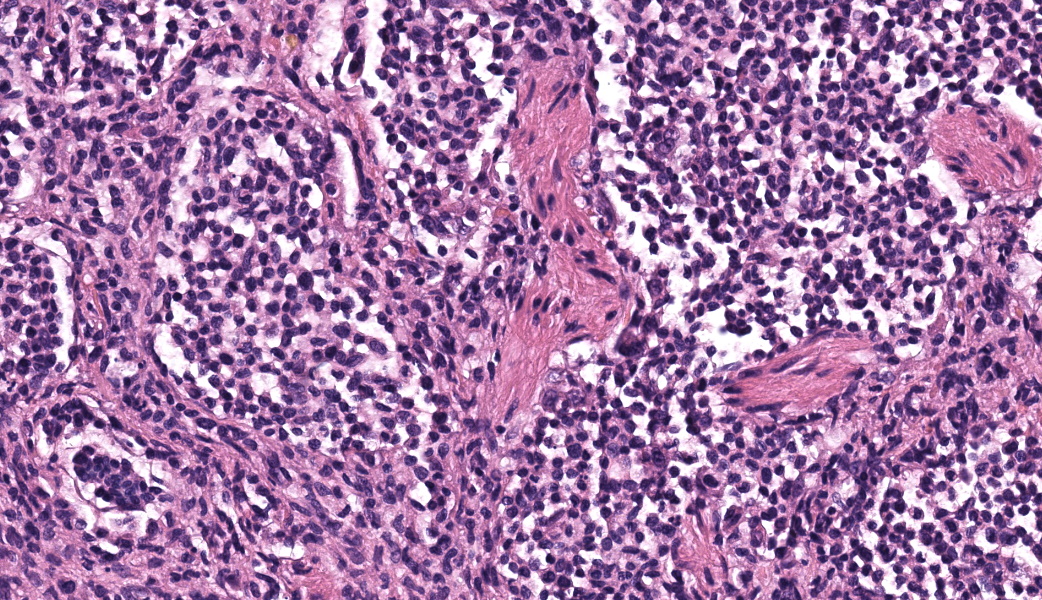

Expanding the airway and alveolar interstitium, subpleural spaces and also filling alveolar spaces, there is a proliferation of large numbers of round-polygonal cells. The proliferative round cell population have a moderate amount of eosinophilic cytoplasm and a reniform nucleus that contains coarsely stippled chromatin and a single nucleolus. There is mild anisocytosis and anisokaryosis, and there are occasional multinucleated cells. There is one mitotic figure per 2.37 square mm. Within the pleural, peribronchiolar interstitium and alveolar septa, the proliferative cells are accompanied by fine strands of collagen, resulting in further expansion of those structures, and in some areas, complete effacement of the normal pulmonary architecture with obliteration of air spaces. In non-consolidated areas, alveolar septa are multifocally ruptured (microscopic emphysema). There is multifocal, moderate, hyperplasia of bronchiolar smooth muscle, and occasionally, especially in subpleural areas, there is type 2 pneumocyte hyperplasia. Medium-sized pulmonary arteries demonstrate hyperplasia of the tunica media. Airway epithelium is frequently sloughed (post-mortem artefact). Gram, Ziehl-Neelson and PAS-stained sections do not highlight micro-organisms.Contributor's Morphologic Diagnoses:

Typical microscopic findings include pleomorphic histiocytic cells that target terminal and respiratory bronchioles and extend into adjacent alveoli.3 Affected bronchioles undergo smooth muscle hyperplasia and there is fibrosis of the alveolar septa. The Langerhans cells demonstrate CD18 and E-cadherin, vimentin and IBA-1positive immunoreactivity.1 In addition, feline Langerhans cells do not react to CD204.7